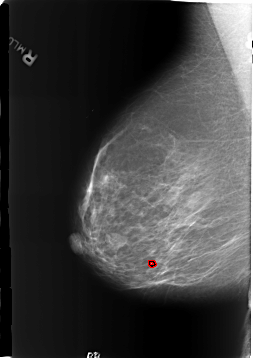

RIGHT_MLO LINES 5720 PIXELS_PER_LINE 4040 BITS_PER_PIXEL 12 RESOLUTION 50 OVERLAY

FILE: B_3186_1.RIGHT_MLO.OVERLAY

TOTAL_ABNORMALITIES 1

ABNORMALITY 1

LESION_TYPE CALCIFICATION TYPE LUCENT_CENTERED DISTRIBUTION N/A

ASSESSMENT 2

SUBTLETY 4

PATHOLOGY BENIGN

TOTAL_OUTLINES 1

BOUNDARY